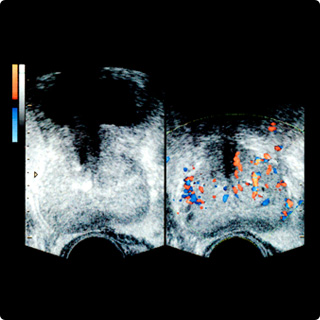

前列腺超声检查

将一根两毫米粗的导管插入股骨血管,以定位为前列腺提供过量供应的血管,并用栓塞材料将其阻塞。

减少流向前列腺的血液,从而减缓前列腺的营养供应,使其逐渐缩小。